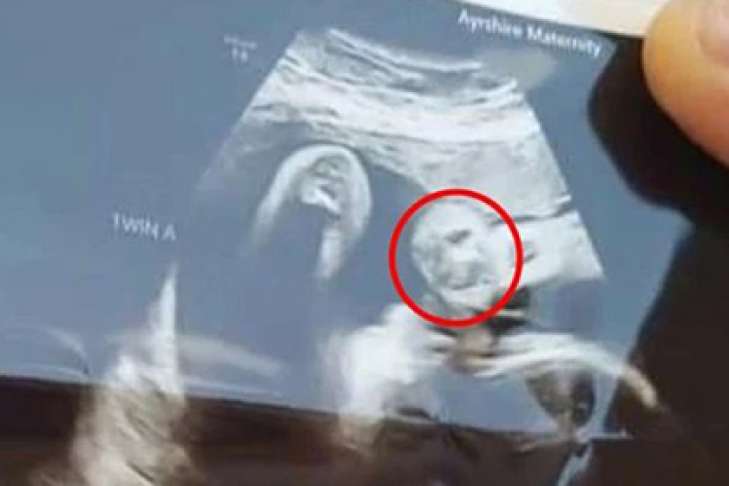

26-летняя мать двухлетнего ребенка Джейми-Ли Ликриш (Jamie-Lee Lickrish) вынашивает двойню. Она испугалась, когда увидела на кадре с УЗИ очертания, напомнившие ей дедушку Томаса Брауна, скончавшегося два года назад.

По словам Ликриш, помимо мужчины, на снимке УЗИ заметен облик женщины с длинными волосами. Она допускает, что это могла быть ее покойная бабушка или мать.